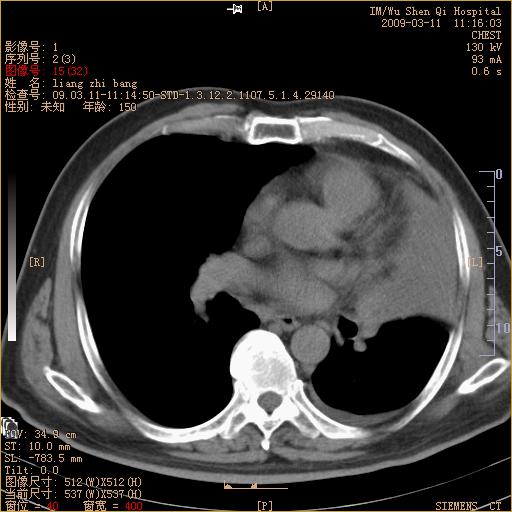

标题: CT18604:男,60岁,咳嗽一月余 [打印本页]

标题: CT18604:男,60岁,咳嗽一月余

1)考虑左肺上叶中央型肺癌并左肺上叶肺不张;建议必要时行纤支镜检查进一步明确诊断。2)左侧胸腔积液。

肺门肿块、支气管开口闭塞伴肺不张及胸水!典型的中心型肺癌变现!

1、左肺上叶中央型肺癌并上叶阻塞性肺不张。

2、左侧胸腔少量积液,右侧胸膜轻度增厚。

左肺们肿块并左肺上叶不张。考虑左肺中心性肺癌并左肺上叶不张及左侧胸腔积液